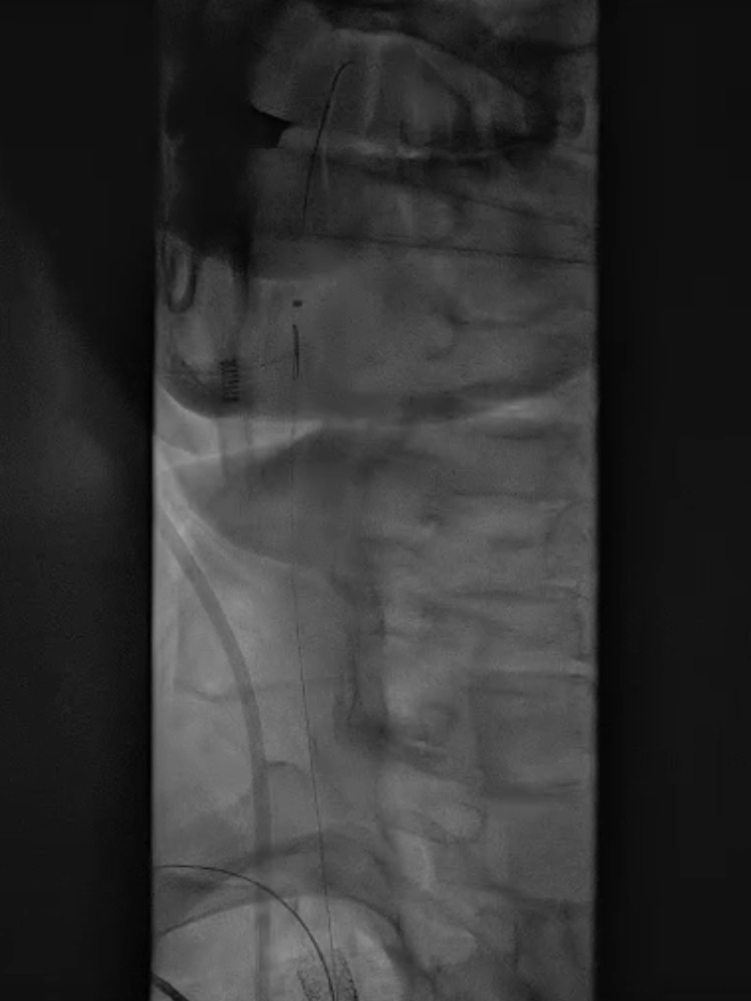

收尾操作:再次以球囊带鞘方式跟进长鞘至支架远端,回收保护伞;最终造影显示支架内血流通畅,右锁骨下动脉、右颈动脉、椎动脉显影良好,椎动脉血流速度较术前明显改善。

长鞘上行困难

回收保护伞

再次球囊带鞘

更进至支架远端

造影支架内通畅

右锁骨下动脉 右侧颈动脉

血流通畅椎动脉显影好